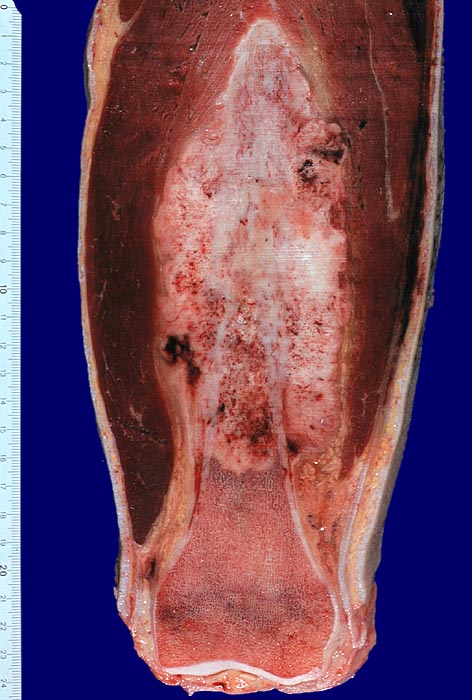

Morphologische Merkmale:

• Tibiametaphyse mit angrenzendem Weichteilgewebe.

• Das Sarkom infiltriert diffus den spongiösen Knochen der Diaphyse und hat präexistente Knochenbälkchen verdrängt.

• Der Tumor hat die Korticalis destruiert und infiltriert die angrenzende Skelettmuskulatur.

• Der Tumor besteht aus neugebildetem bereits verkalktem Knochen oder einem Netzwerk von primitiven Osteoidtrabekeln. Entlang oder innerhalb der Osteoidtrabekel lokalisierte polymorphe Tumorzellen mit ausgeprägten Kernatypien und zahlreichen Mitosen. Leicht verwaschene Kernstrukturen als Folge der Gewebsentkalkung.